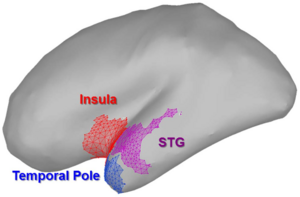

- 3.22 High-field Functional Magnetic Resonance Imaging of Vocalization Processing in Marmosets

- 3.23 Optimizing Parameters of an Open-source Airway Segmentation Algorithm using Different CT Images